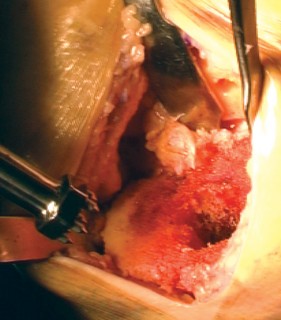

The hallmark of a cemented TKA is the creation of a durable, interlocking micro-mechanical bond between the host trabecular bone and the polymethylmethacrylate (PMMA) bone cement. PMMA is not an adhesive; it functions as a grout. Therefore, meticulous bone bed preparation is the single most critical factor in preventing aseptic loosening. The resected bony surfaces must be aggressively cleansed using pulsatile lavage to remove marrow, fat, and debris, exposing the porous cancellous bone. Sclerotic areas should be perforated with a small drill bit to enhance cement interdigitation.

The bone must be thoroughly dried immediately prior to cement application. High-viscosity cement is typically mixed under a vacuum to reduce porosity and increase fatigue strength. The cement is applied during its "doughy" phase to both the implant surfaces and the prepared bone. The components are then impacted into place.

Crucially, the cement must be pressurized into the cancellous bone to achieve a penetration depth of 3 to 4 mm. Once the components are seated, all extruded peripheral cement must be meticulously removed with a curette, particularly from the posterior aspect of the condyles and the posterolateral corner, where retained cement fragments can cause severe postoperative pain, third-body wear, or impingement. The knee is then held in full extension with axial compression applied until the exothermic polymerization process is complete and the cement is fully cured.